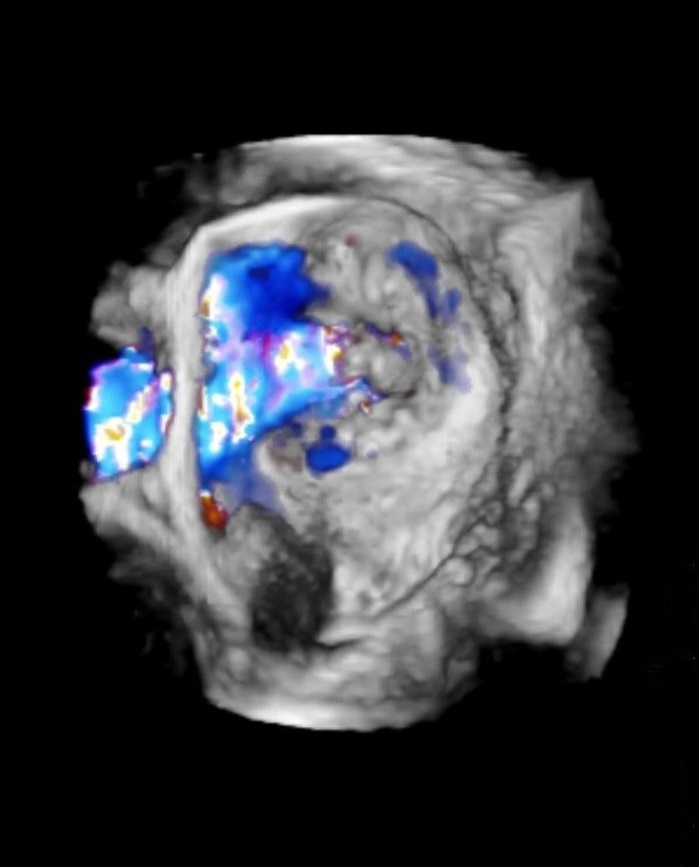

基本は二次元の断層図で評価しますが、必要に応じて三次元の立体像で評価し、手術前の検討などに役立てています。

心臓手術の前には3D経食道エコー図法も駆使し、手術精度向上に寄与しています。